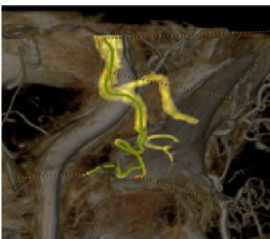

Die automatische Segmentierung von Knochen und Gefäßen und die Mittellinienverfolgung durch den Gefäßverschluss ermöglichen eine schnelle Planung anhand von präoperativen CT- oder MR-Bildern. Durch diese Kombination präoperativer CT- oder MR-Bilder mit Mittellinienverfolgung und Durchleuchtung in Echtzeit können Spezialisten außerordentlich gut sehen, wo die Rekanalisation vorgenommen werden muss und wo sich die Einstichstelle befindet, ohne die Kontrastmittelmenge erhöhen zu müssen.

Vessel ASSIST bietet eine präzise und einfache anatomische Segmentierung und genaue Gefäßquantifizierung anhand von 3D-Volumen. Zudem ermöglichen die erweiterte 3D-Roadmap und erweiterte Bildführungsfunktionen für die frontale und laterale Ebene das sichere Führen von Kathetern.